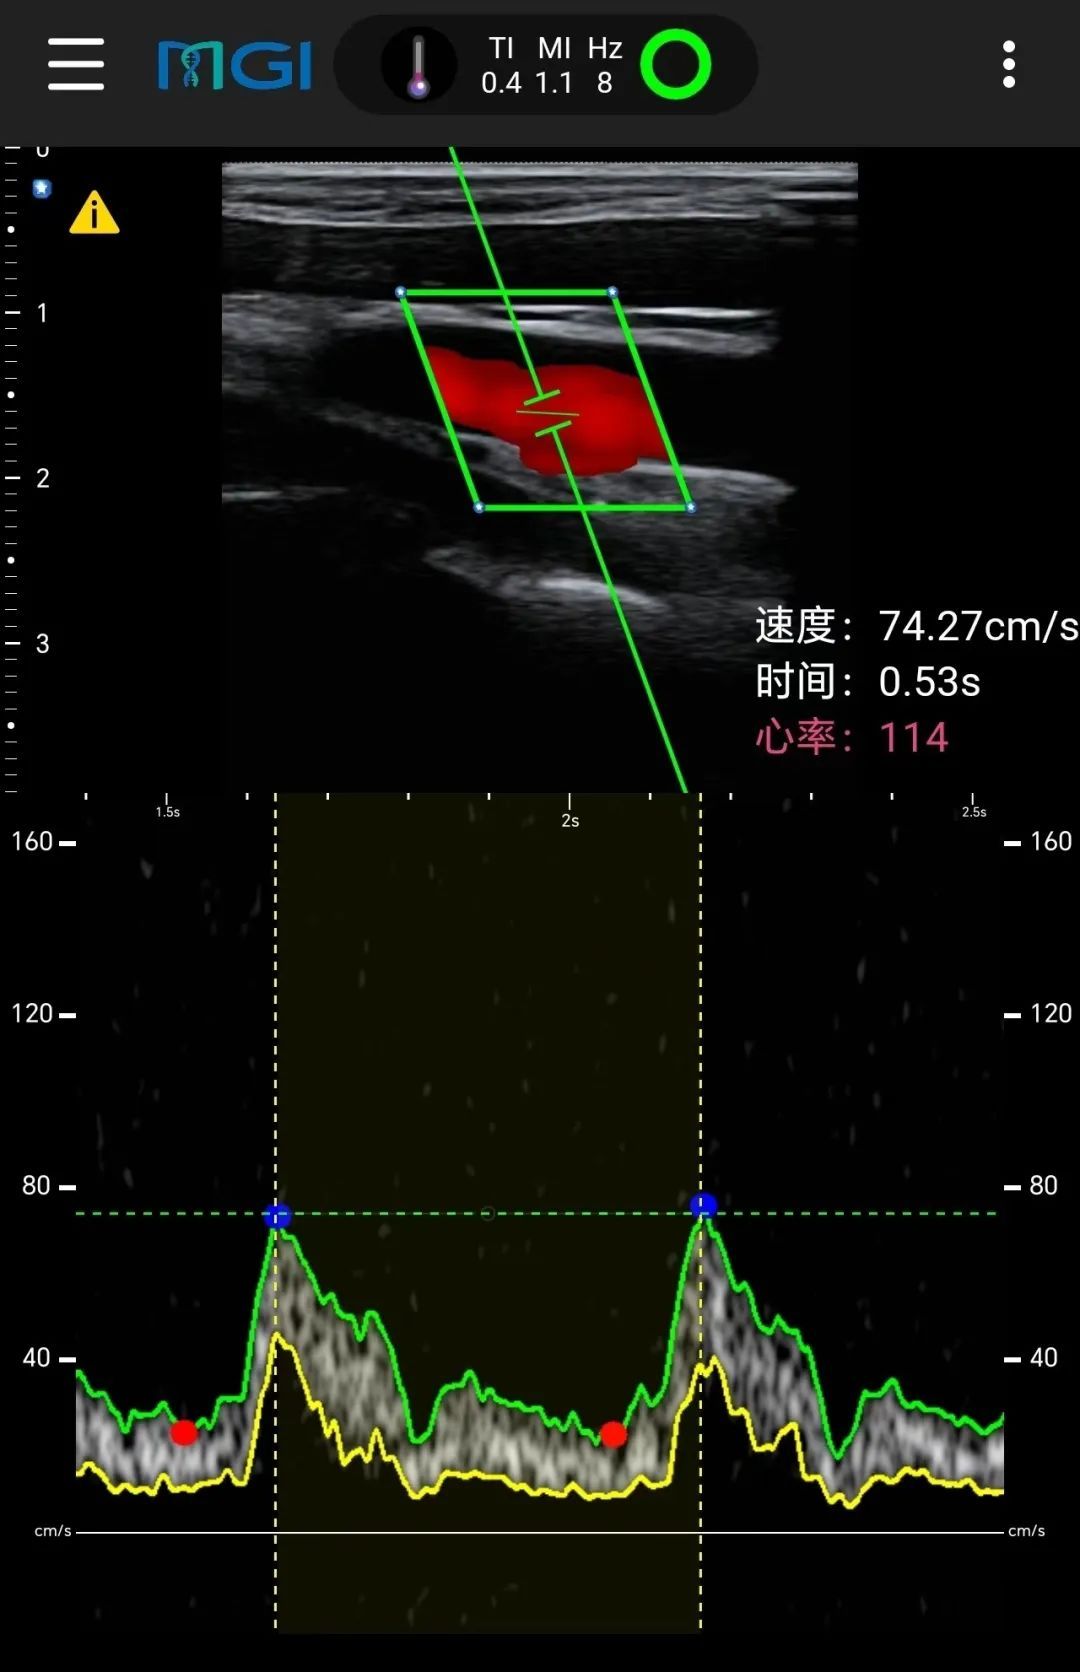

其中,华大智造无线掌上超声自带远程会诊功能。在海拔8300米的营地,华大登山队员使用该设备完成了与远在4000公里外的北京医院超声科主任、2500公里外的四川阿坝临床医生以及4000公里外的深圳团队的连线,成功实现会诊,并对登山队员进行了颈动脉实时超声扫查,以探索颈动脉血流动力学在极端高海拔地区的影响。

值得一提的是,华大智造无线掌上超声还随队登顶珠峰,在峰顶实时获取了登顶队员的颈动脉超声扫查图像,这也是全球首张诞生于世界之巅的超声图。此外,本次在世界之巅首次被记录下来的,还有登山队员的静息态脑电数据。

来自世界之巅的全球首张超声影像图。

1975年5月,全球首位从北坡登顶珠峰的女登山家潘多,从峰顶传回世界上第一份心电遥测图。近50年后的今天,华大登山队从峰顶传回了第一份超声图和脑电数据,希望以更多维度的数据,探究人在高原适应过程和极限攀登前后的生理状态变化。